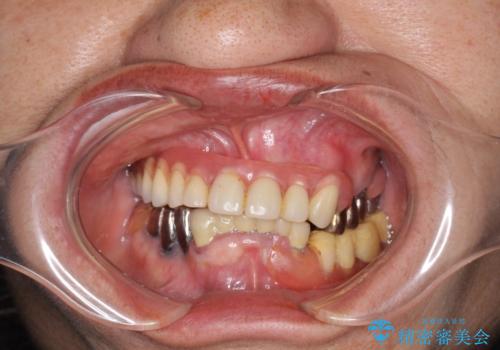

- 他院にて入れ歯を入れたが全体的に左に傾いており、咬みにくく、見た目も気になるといらっしゃった方の症例です。

診査の結果、虫歯が進行し保存できない歯が多かったため抜歯し、磁性アタッチメントを用いたインプラントオーバーデンチャーによる咬合及び見た目の改善を行いました。

磁性アタッチメントとは残っている歯根またはインプラントに磁性金属を埋め込み、入れ歯の裏側(歯肉に触れる側)に小さい磁石を埋め込んで固定させる入れ歯(義歯)のことです。土台となる歯やインプラントに無理な負荷をかけず、磁力によって強力に密着するため、ぐらついたり、ズレたりすることはありません。また総入れ歯だけでなく部分入れ歯にも使用できます。